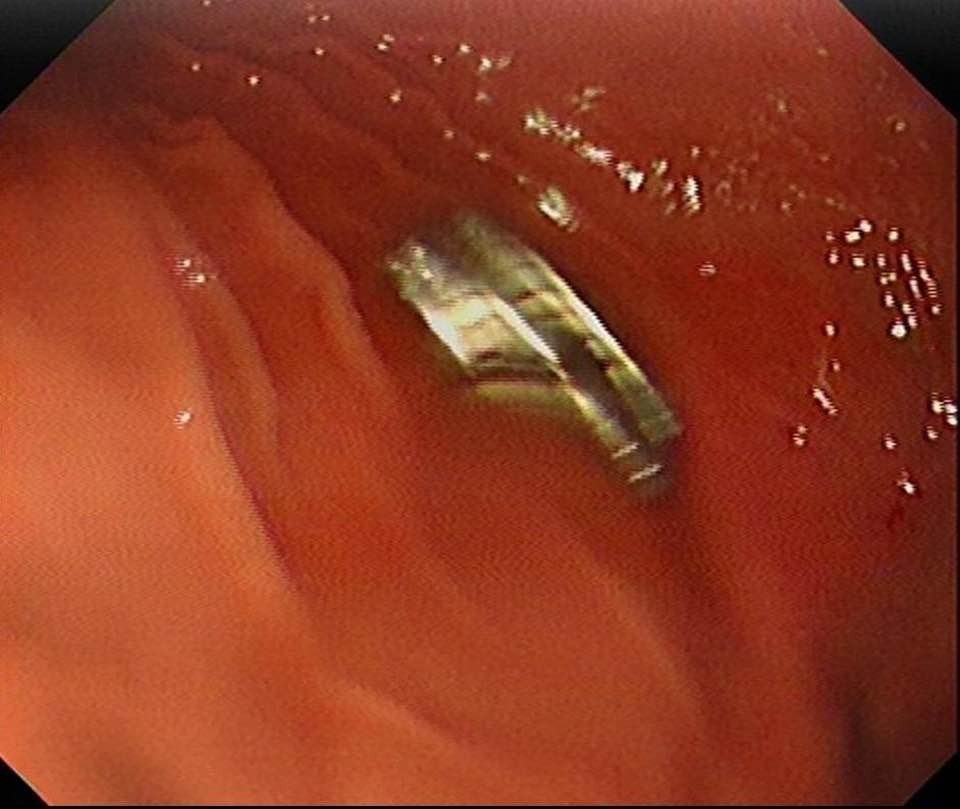

Elazığ’da doktorlar, 3 yaşındaki bir çocuğun yuttuğu 19 mıknatısı başarılı bir operasyonla çıkardı.

Fırat Üniversitesi Çocuk Gastroenteroloji Hepatoloji ve Beslenme Bilim Dalı Başkanı Prof. Dr. Yaşar Doğan tarafından gerçekleştirilen endoskopik operasyonla mıknatıslar çocuğun yemek borusundan çıkarıldı.

Uzun süre yemek borusunda takılı kalan mıknatısların, yemek borusu ve mide girişinde zedelenmelere yol açtığı öğrenildi.